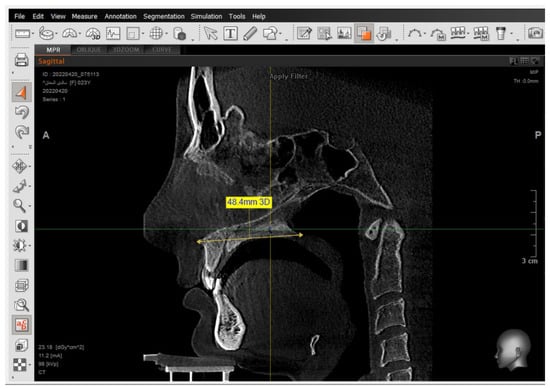

A 2D-Unsharpen filter was chosen after opening the radiograph to control the clearance of bone borders. The planes that were used and drawn were (ANS-PNS) (Go-Me) in the sagittal view, and (J-J) (Ag-Ag) in the frontal view. The green and yellow (axial and coronal plane) were moved to pass through the axis of the tooth (Figure 2 and Figure 3). Then, the orange sagittal plane in the coronal window was moved until it reached the middle of the incisal margin and the apex of the root (Figure 4). Thus, the largest buccal–lingual section of the centrals and canines was obtained in the sagittal view, referring to the buccal alveolar bone crest, detecting any bony defects (Figure 3). The definition of an alveolar defect when the cortical bone is around the vestibular surface of the root refers to the absence of at least three sequential sagittal views [8]. The defect was confirmed by 3D Zoom when the 2D reading was not clear (Figure 5) [32].

Next, a reset to the MPR (Multi-Planar Reconstruction) was performed to measure the distance between the jaw plane and the referred alveolar bone crest (Figure 6) [32].

Figure 6. Measuring the distance between the tip of the buccal alveolar bone crest and the maxillary plane, and measuring the angle formed between the tooth longitudinal axis and the maxillary plane in the sagittal view.